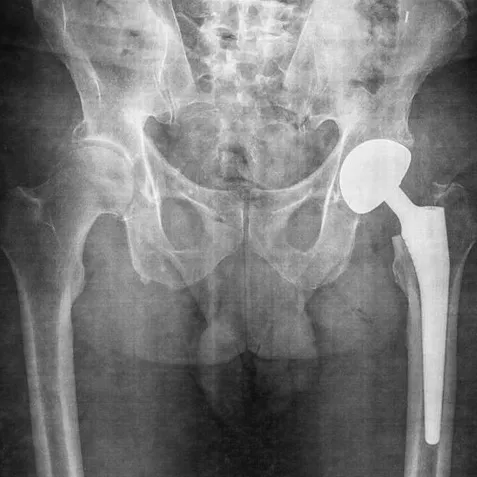

Passez le curseur ou le doigt sur l'image pour afficher l'état de la même articulation 10 ans plus tard.

L'articulation de la hanche fait intervenir les os soudés du bassin (ilium, ischium et pubis) et le fémur. Celui-ci est l'os le plus long et le plus solide du corps humain. La réduction de l'espace articulaire correspond au vieillissement du cartilage.

Selon chatGPT, "après 75 ans : jusqu’à 20 % (des humains) peuvent présenter des signes radiologiques d’arthrose de hanche."

"Coxarthrose" est la fusion d'un mot latin coxa qui veut dire hanche et d'un mot grec άρθρον qui veut dire articulation.